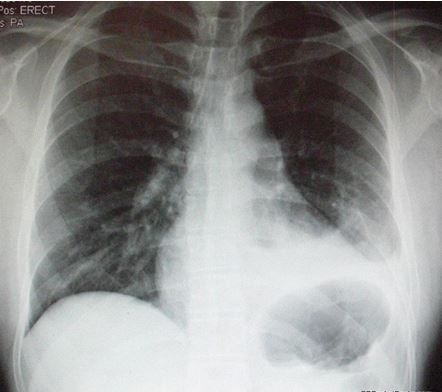

A 44-year-old African American woman was evaluated for symptoms of worsening cough, shortness of breath, chest tightness, and fatigue of 6 months’ duration. Bronchial asthma had been her diagnosis 2 years earlier, and she had been compliant with her inhalation therapy.

The physical exam showed bilateral diffuse wheezing and crackles. An earlier chest radiograph showed mild hilar prominence. A repeated radiograph showed new bilateral diffuse interstitial infiltrates involving both lungs and bilateral hilar lymphadenopathy. This chest CT scan showed similar findings with a tree-in-bud appearance predominantly in the midlung zones and perihilar areas. Pulmonary function testing results showed a progression from moderate to severe obstructive lung disease and worsening diffusing capacity of the lung for carbon monoxide.

Positive findings of sarcoidosis involving the skin along with bilateral diffuse interstitial lung infiltrates and hilar lymphadenopathy supported a diagnosis of pulmonary sarcoidosis.

Sarcoidosis affects the lungs in 90% of cases. It usually involves the intrathoracic lymph nodes and, less frequently, the lung parenchyma. Up to 50% of patients have symptoms similar to those of asthma, such as cough, wheezing, dyspnea, chest pain, chest tightness, and fatigue.